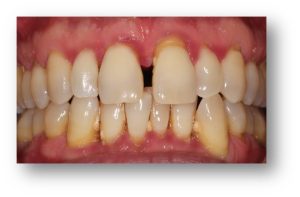

Before and after Periodontal Therapy

![]() | ![]() |

| Untreated severe gum disease | Gum disease treated and stabilised by Dr Halai |